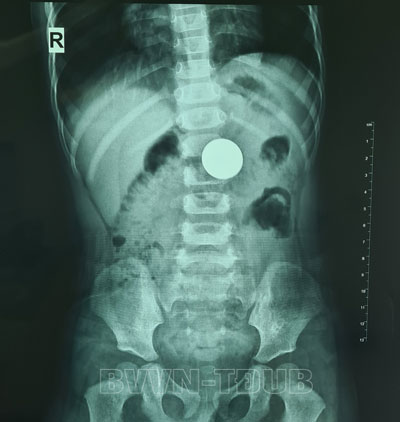

Sau khi tiến hành thăm khám, dựa trên kết quả chụp Xquang ổ bụng, các bác sĩ đã hội chẩn đánh giá dị vật còn đang ở trong dạ dày của bệnh nhi. Rất nhanh chóng trẻ được chỉ định gây mê để nội soi thực quản dạ dày tá tràng cấp cứu để gắp dị vật. Bởi nếu để lâu nguy cơ dị vật có thể di chuyển xuống ruột gây tắc ruột và kéo theo các hậu quả nặng nề khác.

Dị vật của bệnh nhi trên phim chụp X.quang.